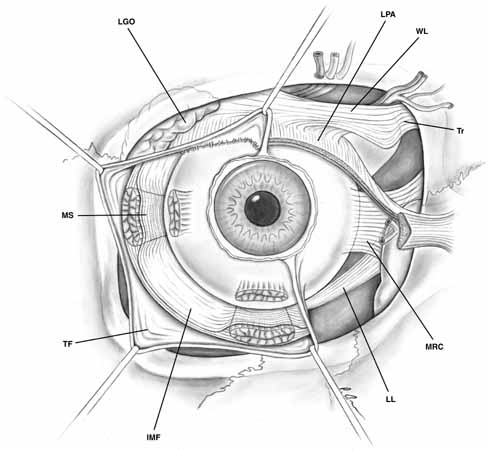

may also cause secondary inflammations of Tenon's capsule.10  Fig. 10 Tenon's fascia, anterior view. Tenon's capsule covers the globe

and extends onto the muscular fascia. Tenon's fascia is denser

between the muscles and thinner toward the posterior aspect of the globe. The

intermuscular septal fascia connecting the muscular sheaths is

demonstrated beneath the reflected Tenon's fascia. (IMF, intermuscular fascia; LGO, lacrimal gland orbital lobe; LL, Lockwood's ligament; LPA, levator palpebrae aponeurosis; MRC, medial rectus check ligament; MS, muscular sheath; TF, Tenon's fascia; Tr, trochlea; WL, Whitnall's ligament) Fig. 10 Tenon's fascia, anterior view. Tenon's capsule covers the globe

and extends onto the muscular fascia. Tenon's fascia is denser

between the muscles and thinner toward the posterior aspect of the globe. The

intermuscular septal fascia connecting the muscular sheaths is

demonstrated beneath the reflected Tenon's fascia. (IMF, intermuscular fascia; LGO, lacrimal gland orbital lobe; LL, Lockwood's ligament; LPA, levator palpebrae aponeurosis; MRC, medial rectus check ligament; MS, muscular sheath; TF, Tenon's fascia; Tr, trochlea; WL, Whitnall's ligament)

|

The muscular fascia ensheathes the extraocular muscles and extends between

them. These muscle fascial sheaths are thin posteriorly but become

much denser anteriorly. The muscular sheaths connect from their extraconal

surface to the orbital walls and from their intraconal surface to

the fibrous septae dividing the intraconal fat lobules.16 The bulbar side of the muscular sheath is thinner than the external aspect

that forms the check ligaments, yet it is thicker than the posterior

portion of Tenon's capsule.17 Smooth muscle fibers are scattered throughout the membrane and are innervated

by the sympathetic nervous system.2

The muscles are connected to the surrounding fascia throughout the anterior

one-third of their lengths, especially where they insert onto the globe,

which prevents their retraction far posteriorly in the orbit if lost during

strabismus operation (unless the muscle has been dissected free). These

attachments account, in part, for the persistent movement of the eye socket

after enucleation when muscles have not been specifically sewn to the

implant. As noted above, each extraocular muscle sheath sends extensions

to the orbital walls. Anteriorly, they are especially prominent and are

called check ligaments. The most developed check ligaments are

those of the medial and lateral rectus muscles (see Figs.

10 and 11). The lateral

check ligament is the strongest and inserts primarily on the posterior

aspect of Whitnall's lateral orbital tubercle with lesser extensions to

the lateral conjunctival fornix and lateral orbital septum. The medial

check ligament inserts on the bone behind the posterior lacrimal crest

and to the medial orbital septum, caruncle, and plica semilunaris. The

superior rectus muscle sheath is joined anteriorly with that of the levator

palpebrae superioris by means of an intermuscular fascia.18

The superior transverse Whitnall's ligament may serve as a superior check

ligament to limit elevation by the upper eyelid19

(see Figs. 10 and 11).